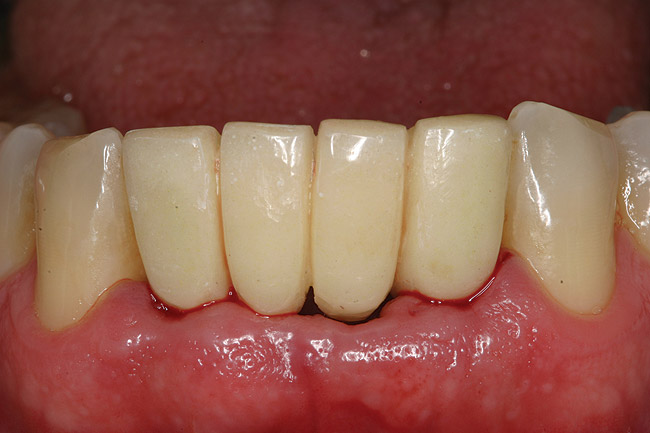

The patient was given postoperative instructions and advised to maintain a soft diet for 6 to 8 weeks to protect the implants. The patient was followed weekly for the first 3 weeks and monthly thereafter. After 4 months of healing, the provisional restoration was removed and the soft tissues were examined. Mature, keratinized gingival tissues were present facially, lingually, and interproximally. Nonkeratinized tissue could be seen at the tissue surfaces of the ovate pontics and in the intrasulcular regions of the implant abutment units. No clinical probing depths beyond 1 mm were found adjacent to the abutments. The healed tissue represented an acceptable clinical result especially in light of the gap that had been present at the time of implant placement (Figure 7A and Figure 7B). Final impressions were made, and the permanent ceramo-metal screw-retained prosthesis was placed within 8 weeks (Figure 8).

Figure 7b  Clinical healing completed.

Figure 7b

Figure 8  Final ceramo-metal restoration.

Figure 8